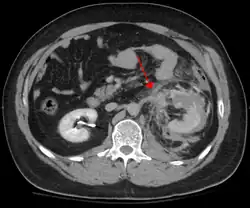

Traumatisme abdominal contondant

Le traumatisme abdominal contondant (TAC) représente 75 % de tous les traumatismes contondants et constitue l'exemple le plus courant de cette blessure[4]. 75 % des TAC surviennent lors des accidents de la route[5], dans lesquels une décélération rapide peut propulser le conducteur contre le volant, le tableau de bord ou la ceinture de sécurité[6], provoquant des contusions dans les cas moins graves, ou la rupture d'organes internes en raison d'une brève augmentation de la pression intraluminale dans les cas les plus graves, en fonction de la force appliquée. Au début, il peut y avoir peu d'indications que des lésions abdominales internes graves se sont produites, ce qui rend l'évaluation plus difficile et exige un haut degré de suspicion clinique[7].

Deux mécanismes physiques de base entrent en jeu dans le risque de lésion des organes intra-abdominaux : la compression et la décélération[8]. Le premier résulte d'un coup direct, tel qu'un coup de poing, ou d'une compression contre un objet non flexible tel qu'une ceinture de sécurité ou une colonne de direction. Cette force peut déformer un organe creux, augmenter sa pression intraluminale ou interne et éventuellement conduire à sa rupture.

La décélération, en revanche, provoque un étirement et un cisaillement aux points d'ancrage du contenu mobile de l'abdomen, comme l'intestin. Cela peut provoquer une déchirure du mésentère de l'intestin et des lésions des vaisseaux sanguins qui parcourent le mésentère. Des exemples classiques de ces mécanismes sont une déchirure hépatique le long du ligament rond et des lésions des artères rénales.